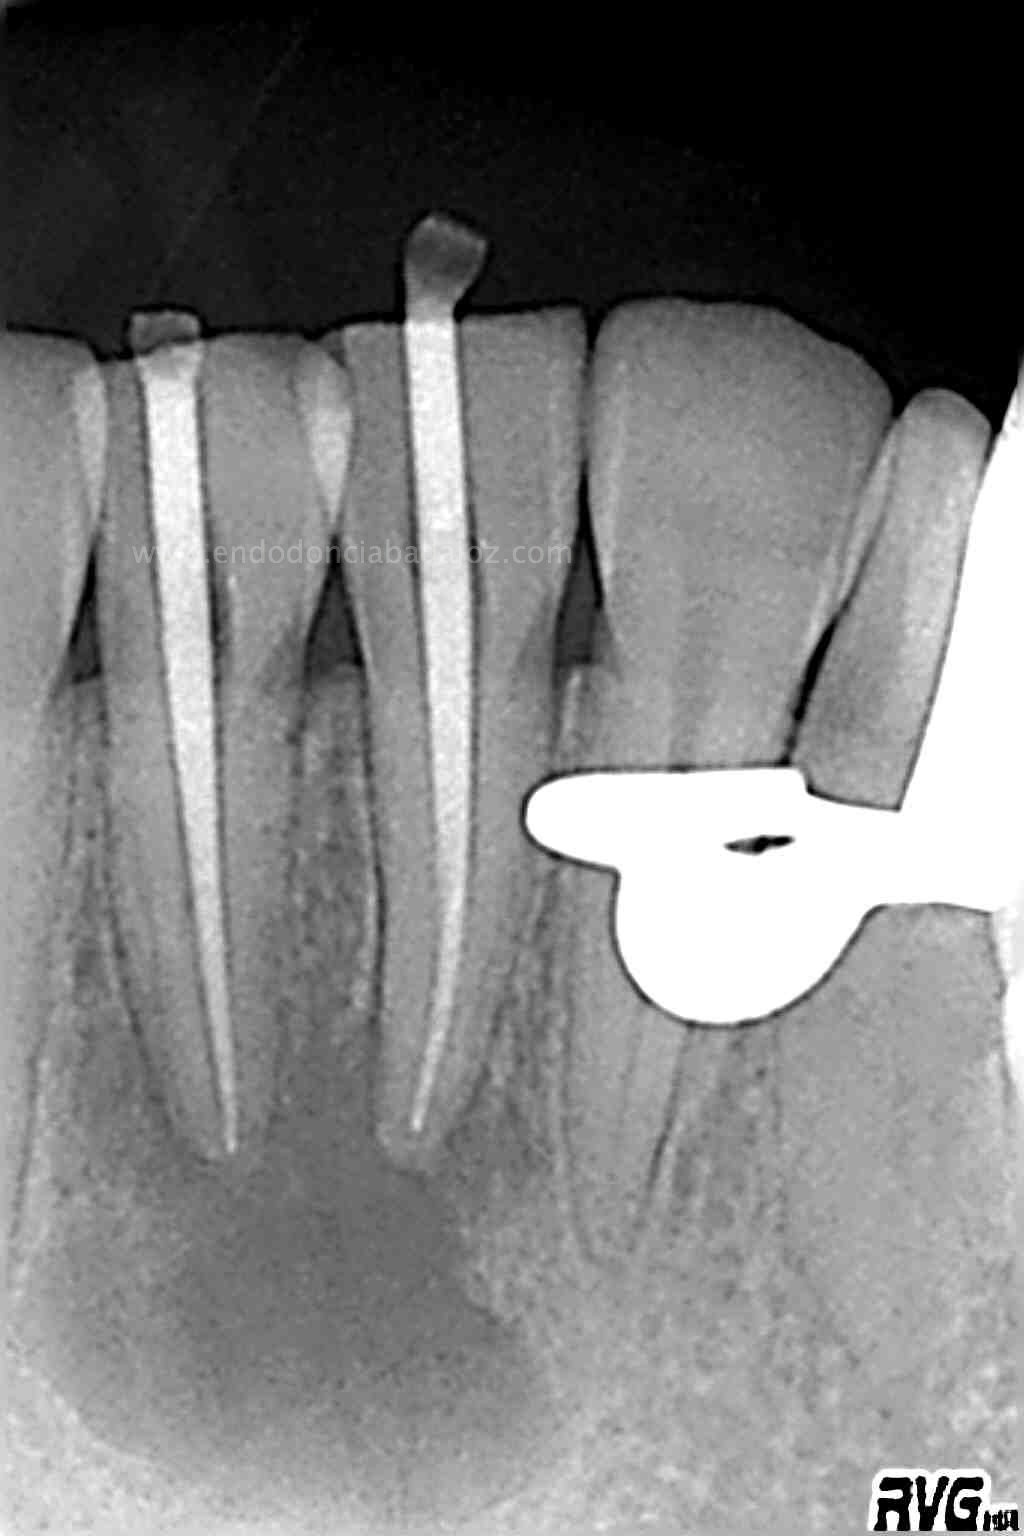

Frente al tratamiento puramente endodóntico, las piezas presentaban vitalidad negativa, fueron tratadas en dos sesiones, rellenando el conducto con Hidróxido de Calcio:

En una segunda sesión, obturamos los conductos tridimensionalmente, conductos acintados. Usaríamos la técnica de Ola continua de Buchanan haciendo un backfilling con la Pistola ObturaII: